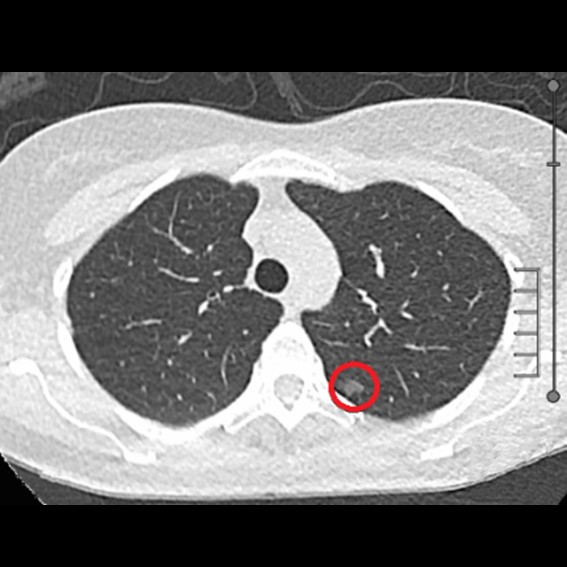

運用高科技尖端影像設備,提供貴賓精準的檢查、判讀、即時醫療、後續追蹤、健康管理或醫學中心轉介服務;從健檢診斷到後端治療,一條龍式服務。永越自成立以來,已服務超過16萬人次,每年通報件數超過千件,揪出包括:甲狀腺癌、肝腫瘤、肺癌、乳癌、子宮頸癌等重大異常的健康警訊,把握住早發現早治療的黃金關鍵。